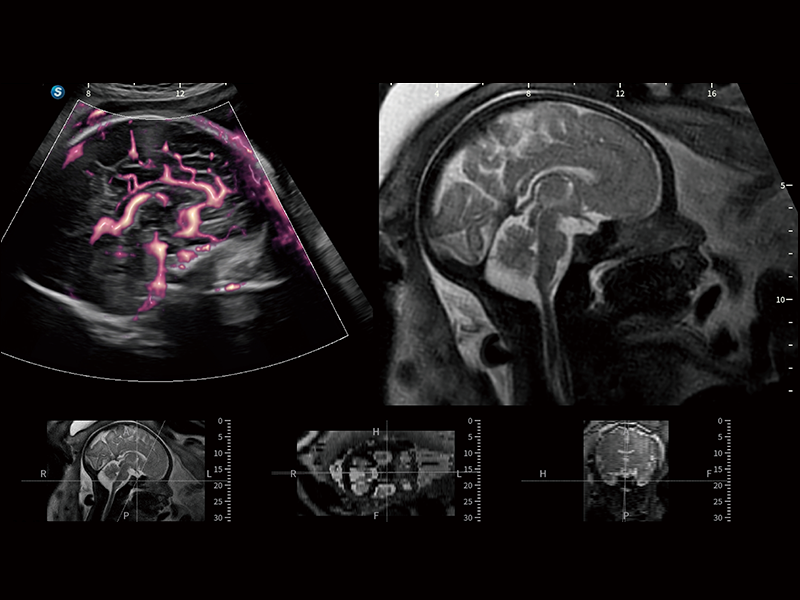

作为开立医疗全新打造的超高端旗舰超声产品,从探头抬起唤醒开启扫查到多维探头发射接收,通过先进的场成像发射、自适应聚合重建等技术,基于RF Data原始射频数据在图像生成、高端功能等方面实现突破,为妇产科、儿科提供全方位临床解决方案。

梦溪®P80以“关爱女性”为基石,提供全方位的解决方案,量身定制以满足女性的健康需求,涵盖妇科、生殖健康检查、产前筛查及产后康复等领域。